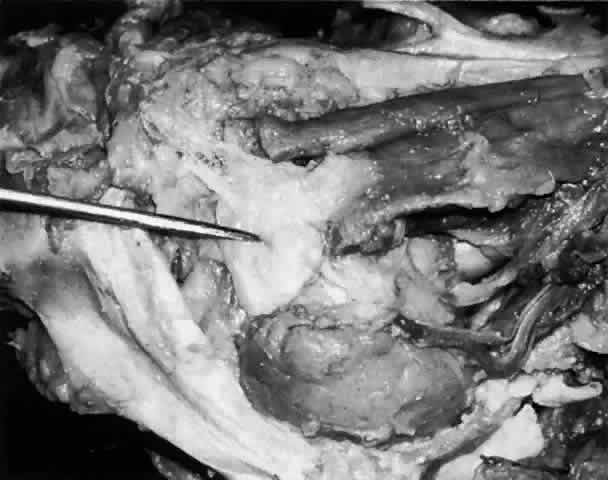

These attachments may become attenuated in older persons, allowing the gland to herniate through a weakened orbital septum to give a temporal bulge in the upper eyelid (Fig. 3). The lacrimal gland tissue is usually grayer and pinker than the surrounding yellow adipose tissue.

Fig. 3. Disinsertion or attenuation of the suspensory fibrous attachments of the lacrimal gland will allow the orbital portion to herniate through a weakened orbital septum, producing a temporal bulge in the upper eyelid.